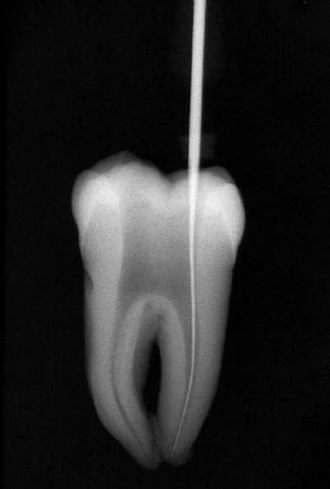

Ở những ống tủy cong, vị trí thành xoang đối diện với đoạn cong chân răng phải được mở rộng (hình 11.14). Nhằm đảm bảo dụng cụ không bị cong hơn so với độ cong vốn có của chân răng. Tương tự như lúc xe chạy vào khúc cua vậy, người ta thường tăng bán kính khúc cua để xe không bị chạy ra khỏi làn đường.

Hình 11.14. A. Phim trước điều trị R36: chân gần cong 1/3 trên. B. Mở đầu bằng trâm số #8 đi vào ống ngoài gần, nhận thấy ống tủy cong về phía xa và phía lưỡi. C. Xoang tủy được mở rộng về phía gần và phía má, phạm vào múi gần ngoài. D. Trâm số #20 có một đường vào thẳng đến 1/3 chóp của ống tủy.